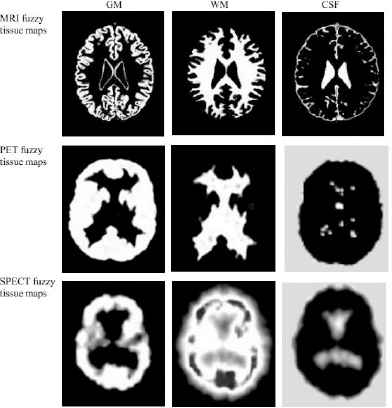

We clustered all images with PCM algorithm, thus obtaining three sets of fuzzy maps: (WMMRI, GMMRI, CSFMRI), (WMPET, GMPET, CSFPET), and (WMSPECT, GMSPECT, CSFSPECT). These maps are related to three distributions of possibility

We clustered the brain images with PCM algorithm for which FCM-AG process has been used for centers initialization. The result obtained from the execution of the PCM algorithm to the image k ∈ {1..P} is a series of three fuzzy maps corresponding to the tissue T∈ {CSF, GM, WM} estimated from the image k, (see Fig. 2). In this figure and in each map, the WM, GM and CSF tissues are expressed by the zones with white color.

Computed fuzzy tissue maps derived from a MR, SPECT and PET images slices.